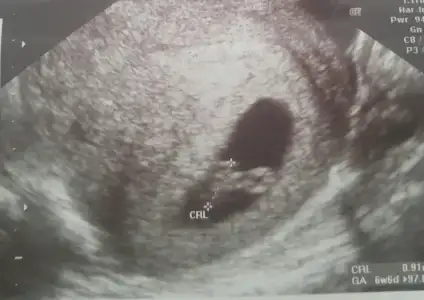

Hazirandaki gebeliğim sonlandı maalesef.pıhtılaşma olmuş ve bebeğimin kalbi durmuş.şimdi allahın izniyle tekrar hamileyim kan suşandırıcı iğne kullanıyyorum.yorum yaparmısınız usg lere.2 side karından .ilk resim 7 hafta 2.si 6+3.

Allah bağışlasın canım.evet karından,bir kızım var 7 yaşında buda 2. Miz :) kızıma kızkardeş mi erkek kardeş mi gelecek bakalım.12.haftada gideceğim tekrar belkş Dr bi tahmin yapar